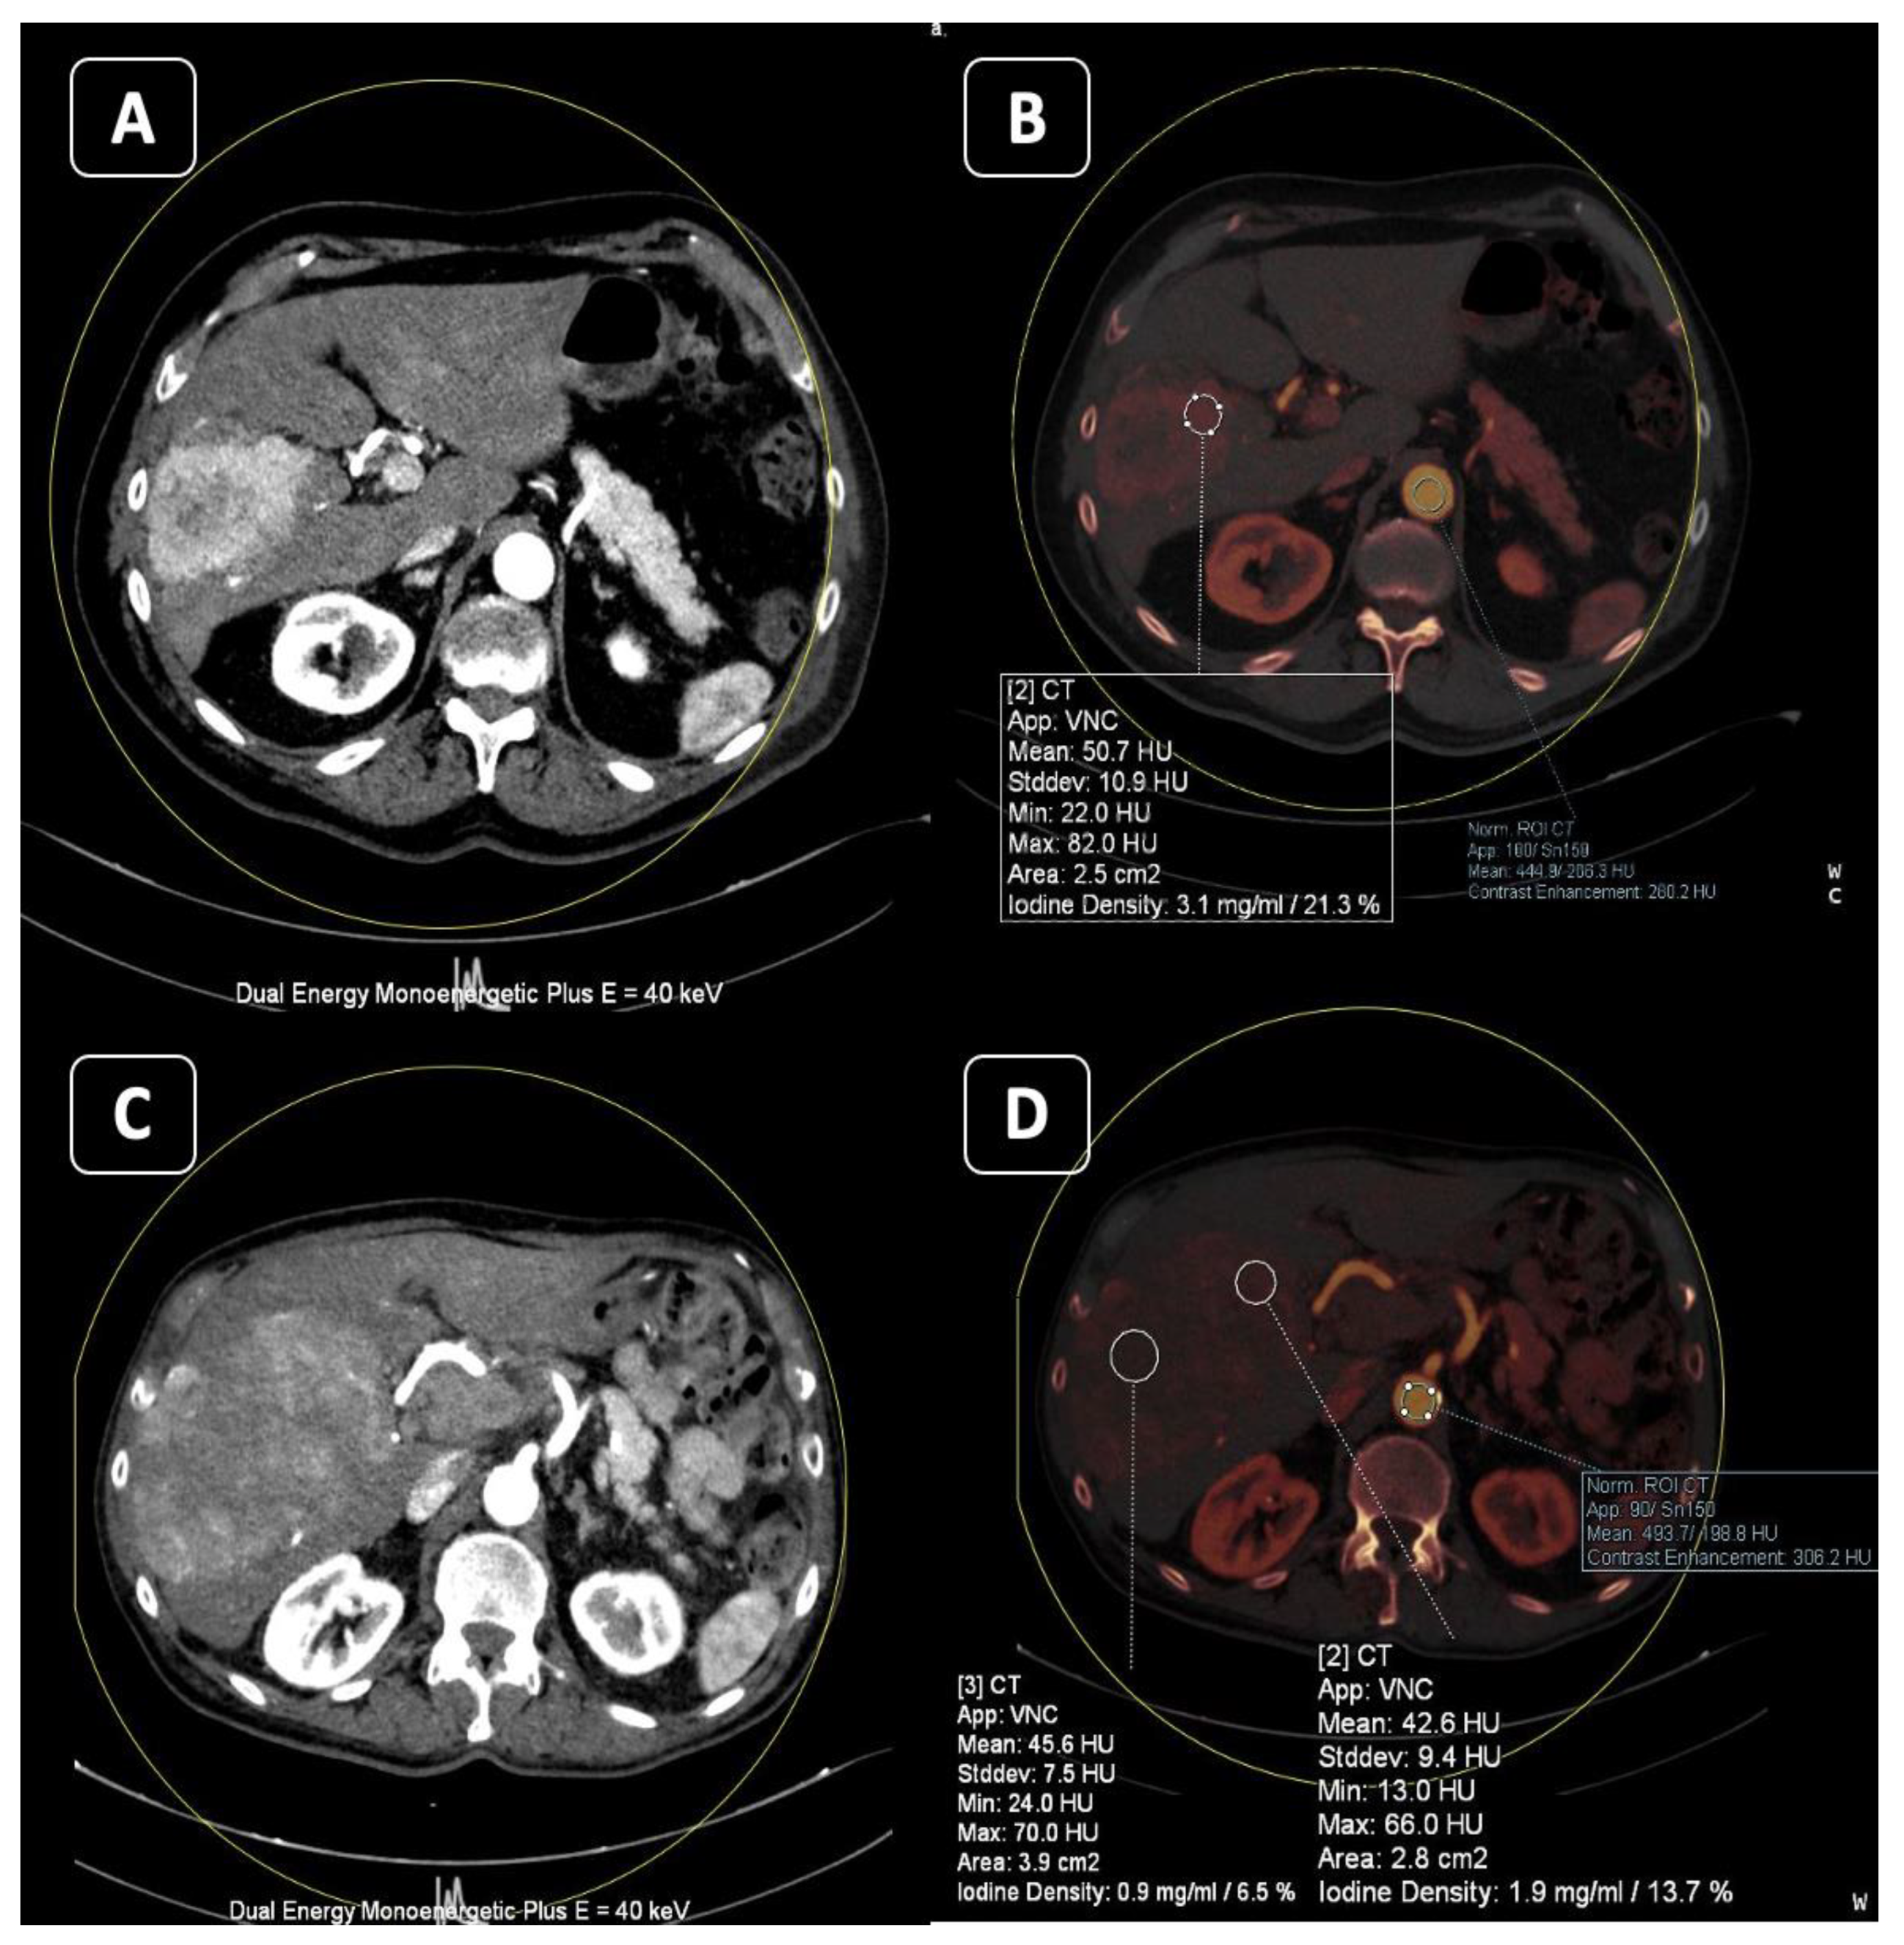

3. Iodine MAP

3.1. Applications

3.2. Response to Therapy